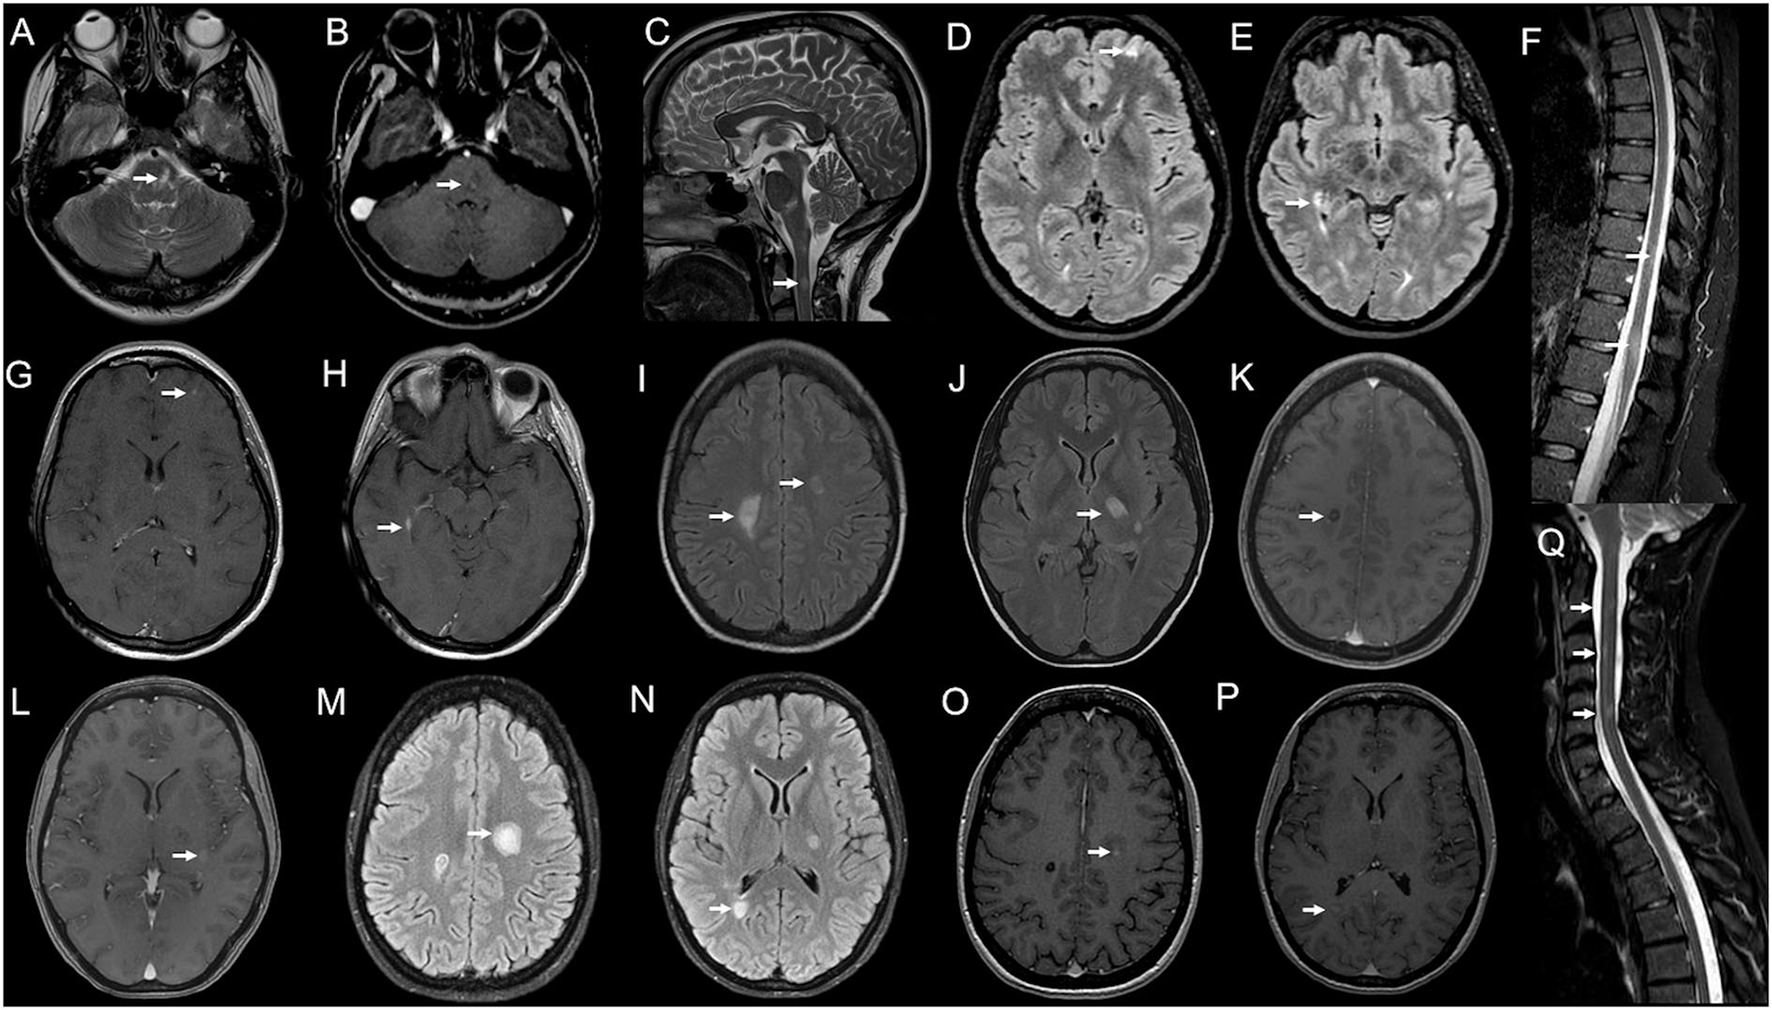

Figure 2

Serial brain and spinal cord MRI scans in Case 3 (A–H) and Case 4 (I–Q). Case 3: (A) Brain MRI performed 25 days after BNT162b2 second dose, showing a T2-weighted hyperintensity (arrow) in the left paramedian mid-pons with blurred enhancement on T1-weighted images [(B); arrow] and a non-enhancing spinal lesion at C2–C3 level [(C); arrow]. (D–H) 2-months MRI follow-up showing two new brain lesions—one juxtacortical in the left frontal hemisphere [(D); arrow] and one periventricular abutting the right lateral ventricle occipital horn [(E); arrow], both with contrast-enhancement [(G,H); arrows] and two spinal lesions at the dorsal level [(F); arrows], with no contrast enhancement (not shown). Case 4: (J–L) Brain MRI obtained 10 days after BNT162b2 second dose, revealing T2-weighted hyperintensities in both centra semiovale (CSO) [(I); arrows] and left thalamus/posterior limb of the internal capsule (IC) [(J); arrow]; lesions in the right CSO [(K); arrow] and left IC [(L); arrow] showed blurred contrast enhancement on T1-weighted images. (M–P) 20-days MRI control showing the enlargement of the left CSO lesion [(M); arrow] and a new lesion in the right peritrigonal area [(N), arrow], both with gadolinium-enhancement on T1-weighted images [(O,P); arrows]. (Q) Spinal cord MRI—obtained 10 days after the brain exam—showing three blurred areas at C2, C3, and C5–C6 levels on STIR sequences, with no enhancement (not shown).

A 40-year-old woman, with a history of renal cell carcinoma and no other comorbidities, received the first dose of the BNT162b2 vaccine on 5th May 2021, and the second dose 5 weeks later. Ten days after the first dose, she presented with numbness in her hands progressively extending to all the upper limbs. On 4th July −25 days after the second dose—she developed diplopia in her left horizontal gaze. She was admitted to the emergency unit and an abduction deficit in her left eye was found. A brain and cervical spinal cord MRI showed a T2-weighted hyperintensity with blurred enhancement in the left paramedian mid-pons (Figures 2A,B) and a non-enhancing cervical spinal lesion at C2–C3 level (Figure 2C). She was administered a 5-day course of high-dose IVMP and almost completely recovered within 1 week. Two months of the brain and spinal cord MRI control showed two new enhancing supratentorial lesions—one juxtacortical in the left frontal hemisphere and one periventricular abutting the right lateral ventricle occipital horn—and two spinal lesions at the dorsal level, with no contrast enhancement (we cannot define their time of onset as the first MRI lacked a dorsal study; Figures 2D–H). Blood counts and C-reactive protein were normal. Anti-AQP-4/anti-MOG and antibodies for connective tissue diseases were negative. Serum panel for infectious diseases was unremarkable, except for Epstein-Barr Virus (EBV) serology resulting positive for anti-EBV VCA IgM (titer 75.3 U/ml), VCA IgG (>750 U/ml), EBNA IgG (239 U/ml), while EBV EA IgG was negative (9 U/ml). CSF analysis revealed normal cell count, protein, and glucose, and no infectious agent (including EBV) was detected at CSF PCR; CSF IEP showed the presence of 12 OCB (pattern II). She was diagnosed with MS and Natalizumab was started.

A 27-year-old woman, with no previous clinical history, received the first dose of BNT162b2 vaccine on 16th June 2021 and the second dose after 21 days. One week later she reported mild weakness in her left leg spontaneously resolving in 10 days. A few days later, she developed a right facio-brachial motor deficit and dysarthria. She was admitted to the emergency unit and a brain MRI revealed T2-weighted hyperintensities in both centra semiovale (CSO) and left thalamus/posterior limb of the internal capsule (IC); lesions in the right CSO and left IC showed blurred contrast enhancement (Figures 2I–L); spinal cord MRI was negative. CSF analysis revealed normal cell count/protein level and a negative extensive infectious panel, while IEP showed the presence of OCB (pattern II). Serum anti-AQP-4/anti-MOG antibodies resulted negative as well as connective tissue diseases panel except for the positivity of anti-nuclear antibodies (titer 1:160), considered a non-specific finding. Visual evoked potentials did not show abnormalities. She was administrated a 5-day course of high-dose IVMP, with complete recovery. One week later, she complained of right side weakness again—this time involving her leg also—and dysarthria. She started assuming OCS with no improvement. A new brain MRI revealed a new active lesion in the right peritrigonal area and an increase in the size of the previously detected lesions in the left CSO—this time gadolinium-enhancing—whereas areas in right CSO and left IC showed no more enhancement (Figures 2M–P). A spinal cord MRI—performed 10 days after—revealed the presence of three not enhancing cervical areas (at C2, C3, and C5–C6 levels; Figure 2Q). She was diagnosed with MS, and a second 5-day course of high-dose IVMP followed by OCS tapering was administrated. Poor clinical response was obtained and five plasma exchange (PEX) sessions were performed, with a resolution of dysarthria and slight recovery of right hemiparesis. At 2-months of MRI control, the left CSO and right peritrigonal lesions were still contrast-enhancing and a 3-day course of high-dose IVMP was administrated. She promptly started physical therapy with marked improvement in motor performance. She received the first cycle of Cladribine in October 2021. At the three-month follow-up, she almost fully recovered, only showing right-side brisk reflexes and mild oscillations at the position test in her right leg [Expanded Disability Status Scale (EDSS) score 1].